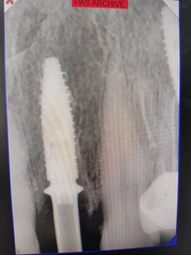

After implant placement (Figure 9), the primary stability of the implant was satisfactory (greater than 35N), the provisional abutment was fixed (Figure 10) and a post-operative retroalveolar radiograph was taken for radiological control of the implant and adaptation of the provisional abutment (Figure 11).

Figure 10. Fixing the temporary abutment to the implant

Figure 11. Postoperative retroalveolar radiography